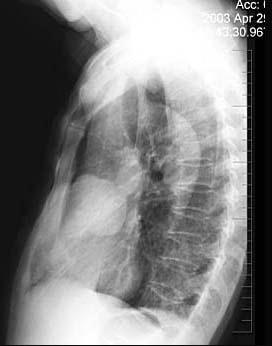

问题 女性,57岁,因胸痛,咳嗽1个月就诊,不发热,咳白色痰,无痰中带血,X线检查见图,最可能的诊断是 ( )

选项 A.右侧肺不张 B.右肺炎症 C.纵隔肿瘤 D.右肺肿瘤 E.间质性肺疾病

答案 D